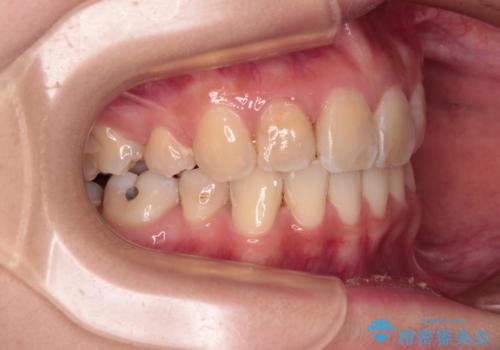

デコボコと深い咬み合わせ ワイヤー装置での抜歯矯正

- 内側に倒れ込んだ歯や下の前歯が隠れてしまうほどの咬み合わせを改善したいとのことで来院された患者様です。

下顎の叢生を解消するために抜歯が必要であり、奥歯の咬み合わせや口元の印象から、上顎も同様に抜歯と判断し、上下左右の第1小臼歯4本抜歯してワイヤー装置にて矯正治療を行うこととしました。